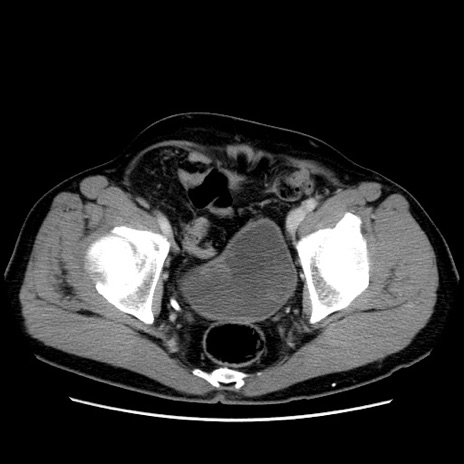

症例34(横断像)

【症例】60歳代 男性

【主訴】右鼠径部膨隆

【現病歴】1年程前より右鼠径部膨隆あり。自己にて還納可能だったため放置していた。3時間前より右鼠径部の脱出を認め、還納困難となり受診。

【既往歴】高血圧

【身体所見】右鼠径部に小児頭大の膨隆あり。弾性硬であり、用手還納は困難。左鼠径部にも膨隆を認める。脱出はなし。

【データ】WBC 15500、CRP 測定なし